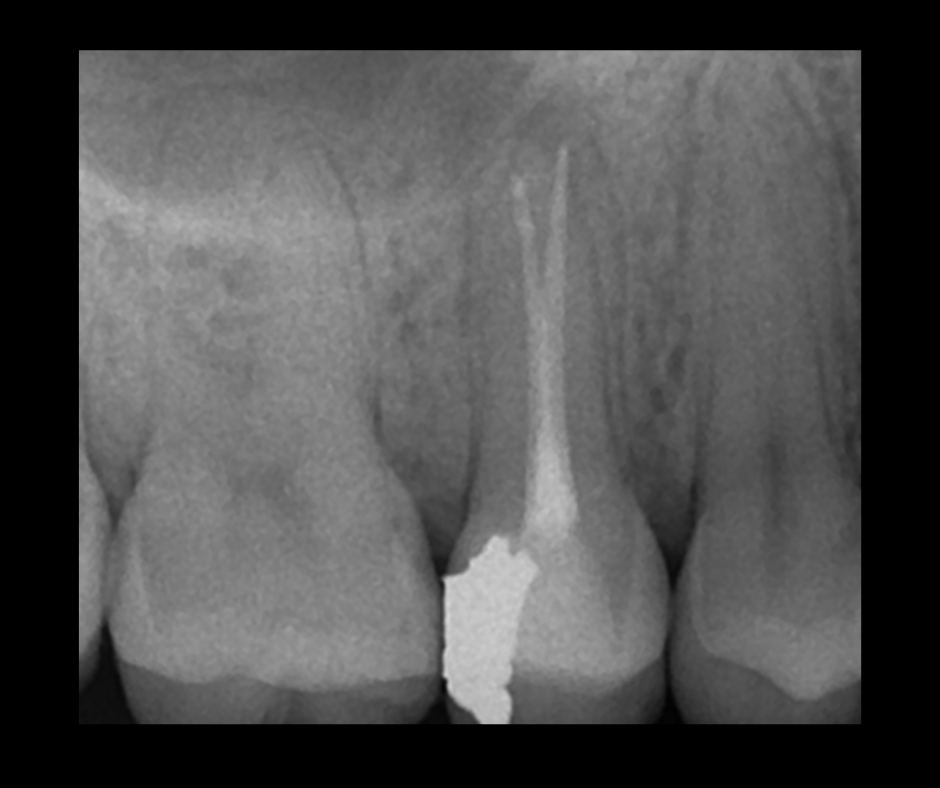

This course focuses on modern single-file endodontic systems, guiding participants through diagnosis, case assessment, access cavity design, canal location, root canal system preparation, and obturation techniques.

• To re-examine access cavity design and its importance in endodontic success

• To understand the importance of achieving patency and mechanical glidepath with hand & NiTi instruments

• To gain confidence in mechanical preparation using rotary and reciprocating NiTi shaping instruments

• To gain confidence in endodontic obturation and develop an understanding of various obturation techniques and methods of developing predictable, reproducible endodontic obturation